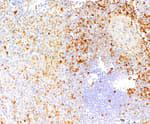

Mouse anti-PCNA Monoclonal Antibody, Purified [PC10]

Bethyl Laboratories Catalog # A500-024A A500-024A-T A500-024ACF

ValidatedDocuments (8) Citations ()Mouse anti-PCNA Monoclonal Antibody, Purified [PC10]

Validation Performed

All Bethyl Laboratories® antibodies are validated to meet our strict performance standards.

Target: PCNA

Reactivity: Human, Mouse

Applications:

Platforms: COMET™

Host: Mouse

Conjugate:

Purity:

For ordering information, see our International Distributors

Product has been discontinued